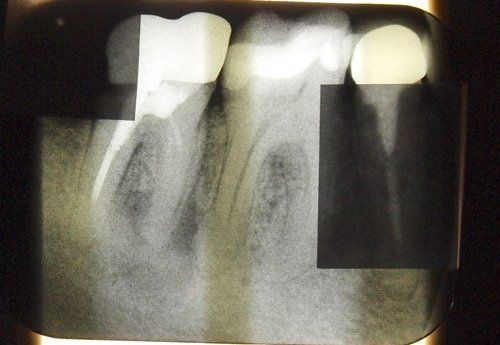

Зуб под коронкой. Корни запломбированы. Зуб был разрушен и врач его наращивал, вкручивая в корни штифты, и наращивая его для коронки. Теперь все признаки периодонтита - снимок еще не делал, но уже чувствую. Несколько дней зуб побаливал, бывало и таблетки пил, было больно надкусывать, ощущение приподнятого зуба. Сейчас практически не болит, на прикус почти не реагирует, но болезненность и уплотнение на челюсти в районе корней. Легкая припухлость на щеке - кто не знает, не заметит.

Есть ли шанс спасти зуб? После штифтов это возможно?

У вас абсолютно правильные мысли, касаемые периодонтита . Штифты необходимо извлечь и, естественно, данная аномалия лечится только через канал. Тем более, что жалеть особо нечего, так как восстанавливать коронковую часть зуба методом штифтов крайне не правильно. Извлеките штифты, перелечите зуб и восстановите зуб вкладкой и коронкой.